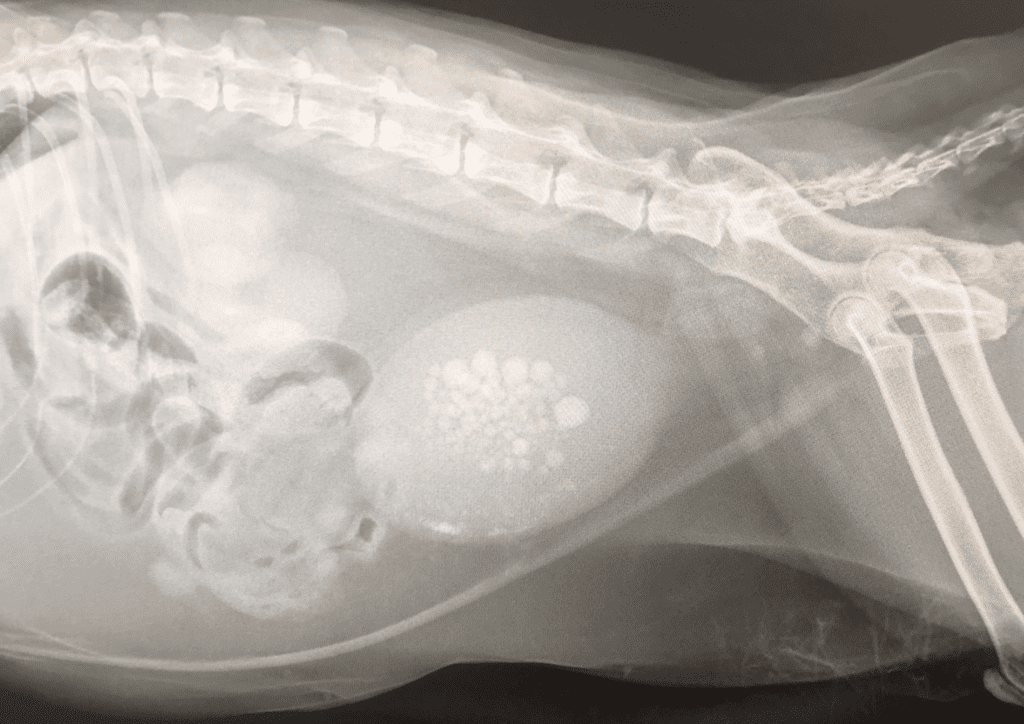

However, as days went by, it was clear that something more serious was at play. Trusting my cat-mom intuition, I sought a second opinion. The news was shocking—Nana had a handful of kidney stones in her bladder, and emergency surgery was needed to save her life. In this article, I will share my experience and discuss the signs, symptoms, and prevention of urinary problems in cats. Additionally, I have an exciting opportunity for you to receive free urinary care cat food. So, keep reading to get all the details.

After undergoing emergency surgery, Nana, my beloved cat, managed to pull through. As the veterinarian finished the procedure, they presented me with a handful of kidney stones—astonished by the sheer quantity they had extracted. The vet informed me that such an abundance of kidney stones is typically more prevalent in male cats, making Nana’s case even more remarkable. Although her bladder had been repaired, there were lingering concerns about her survival. The following week was a rollercoaster of uncertainty, but against all odds, Nana rallied and made a remarkable recovery, going on to enjoy another three years of life.